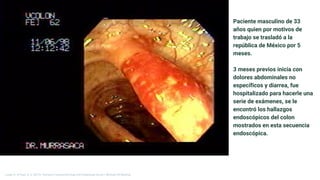

Paciente masculino de 33

años quien por motivos de

trabajo se trasladó a la

república de México por 5

meses.

3 meses previos inicia con

dolores abdominales no

específicos y diarrea, fue

hospitalizado para hacerle una

serie de exámenes, se le

encontró los hallazgos

endoscópicos del colon

mostrados en esta secuencia

endoscópica.